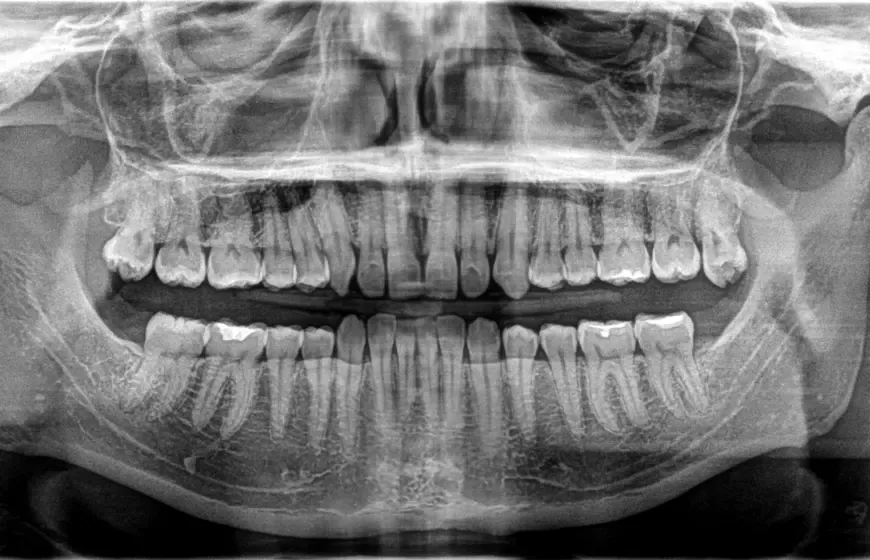

Pantomogram (OPG): kiedy potrzebny jest ogólny obraz wszystkich zębów i szczęki?

Pantomogram, czyli zdjęcie panoramiczne (OPG), to przeglądowe zdjęcie rentgenowskie, które obejmuje wszystkie zęby (zarówno górne, jak i dolne), żuchwę, szczękę, stawy skroniowo-żuchwowe, a także częściowo zatoki szczękowe. To badanie jest niezwykle cenne, gdy potrzebuję ogólnej oceny stanu uzębienia i struktur kostnych. Zalecam je w przypadku planowania leczenia ortodontycznego, implantologicznego, chirurgicznego (np. ekstrakcji ósemek) oraz jako badanie przesiewowe do wykrywania ukrytych patologii, takich jak torbiele czy guzy.

Zęby mądrości, czyli ósemki, często sprawiają wiele problemów. Bardzo często są one zębami zatrzymanymi, co oznacza, że nie wyrżnęły się prawidłowo i pozostają częściowo lub całkowicie ukryte w kości. Zdjęcie RTG, zwłaszcza pantomograficzne, jest absolutnie niezbędne do oceny ich położenia, kierunku wzrostu oraz wpływu na sąsiednie zęby i struktury anatomiczne, takie jak nerw żuchwowy czy zatoka szczękowa. Dzięki temu mogę podjąć decyzję o konieczności ekstrakcji i zaplanować zabieg w bezpieczny sposób.

Dla ortodonty RTG, a zwłaszcza pantomogram i cefalometria, to fundament diagnostyki. Dzięki tym badaniom mogę dokładnie ocenić wady zgryzu, analizować rozwój szczęk, położenie zębów stałych i zawiązków zębów. Na podstawie szczegółowej analizy obrazów rentgenowskich jestem w stanie stworzyć indywidualny i skuteczny plan leczenia aparatem ortodontycznym, który doprowadzi do prawidłowego zgryzu i estetycznego uśmiechu. Bez RTG, leczenie ortodontyczne byłoby znacznie trudniejsze i mniej przewidywalne.